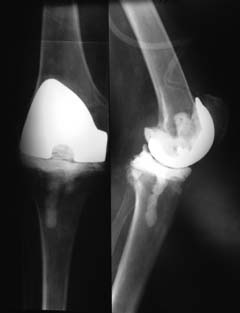

Уважаемые коллеги! Пациент мужчина 62 года эндопротезирование коленного сустава в

сентябре 2011 в одном из соседних учреждений. Множественные операции по восстановлению

связок в анамнезе

Под наше наблюдение попал спустя 3 месяца с клиникой глубокой перипротоезной инфекции.

Гнойный свищ, MRSA в посеве. Выполнено удаление протеза, некрэктомия, установка

цементного спейсера. Заживление первичное, а\б терапия по посевам, в течении 2 месяцев

положительная динамика, нормализация лабораторных показателей. В последующем усиление

болей, отек, разрушение спейсера по рентегнограммам. Взят в операционную для повторной

некрэктомии, удаления спейсера. Во время операции выявлено- отсутствие явного гнойного

содержимого, ткани более жизнеспособные чем во время первого удаления, отсутствие

значительного прогрессирования костных дефектов. Решено от одномоментного артродеза

воздержаться, конечность стабилтзирована дистракционным аппаратом. В

интраоперациооных посевах St.aureus В настоящее время две недели после операции, встает

вопрос о возможностях далнейшего лечения. Ревизонное колено? Еще раз после спейсера или

сразу? Или артродез